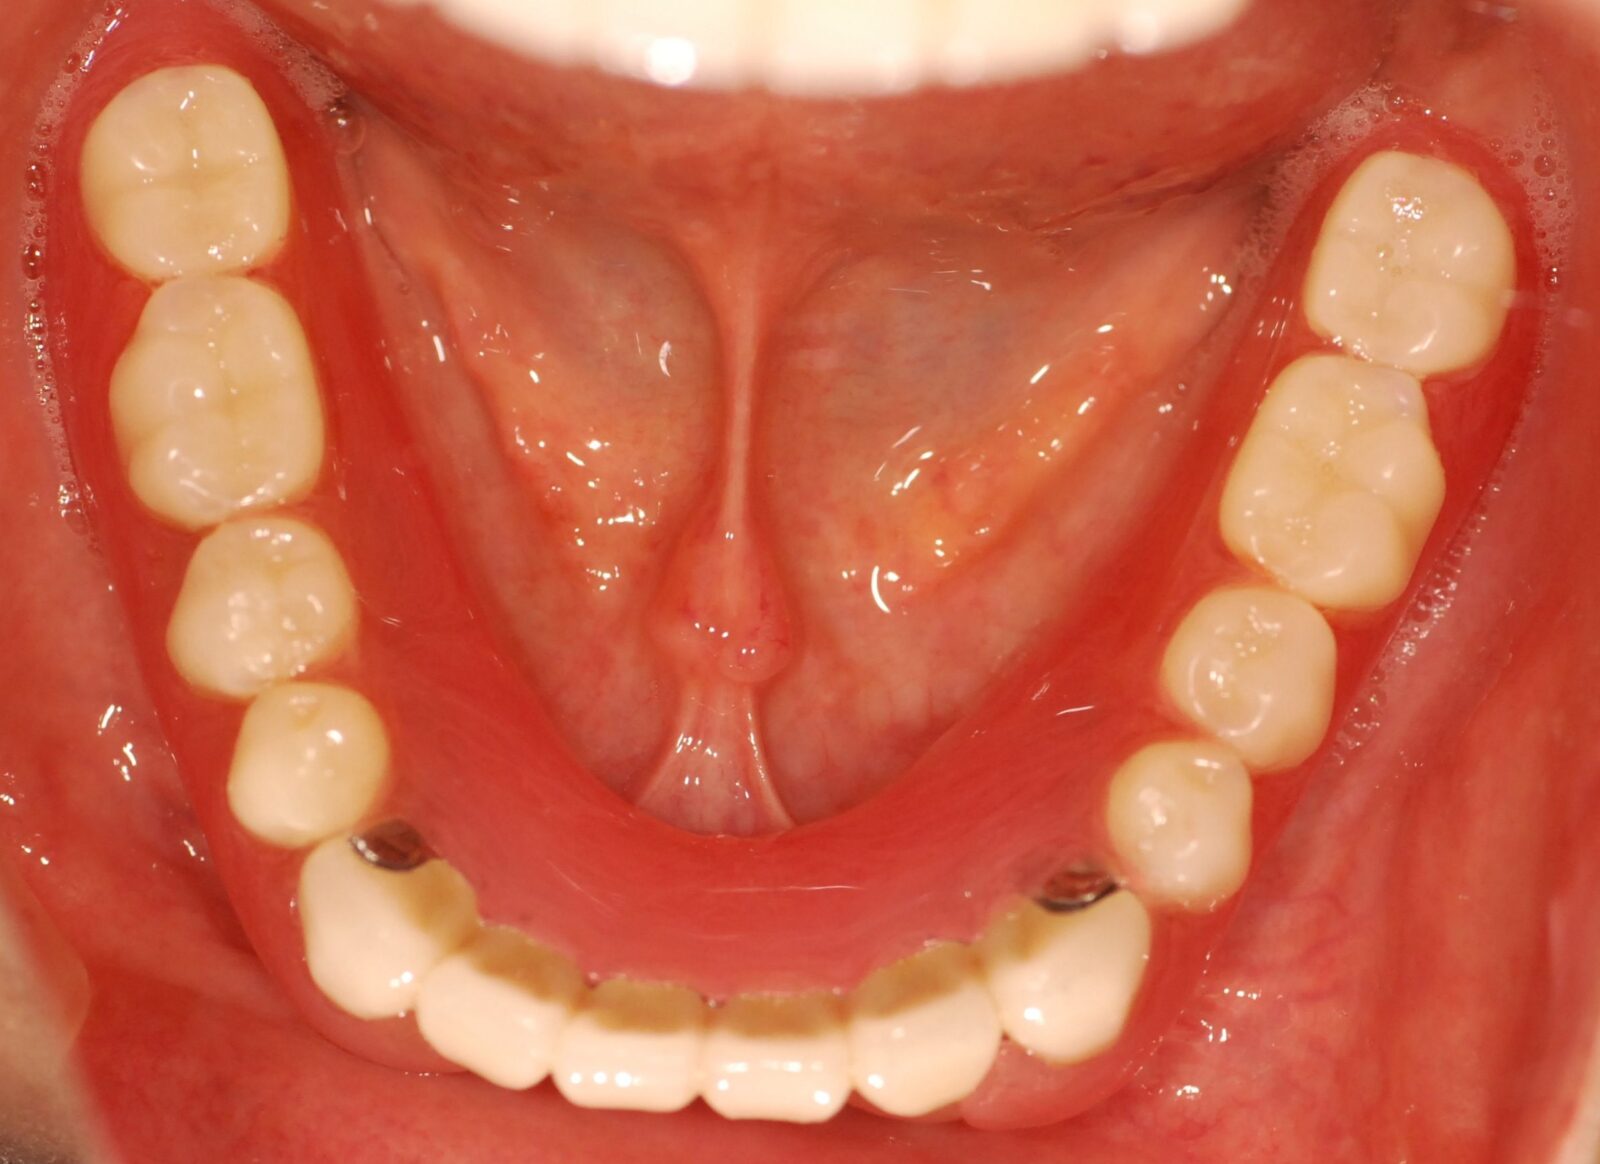

次の写真は、当院で製作した磁性アタッチメント義歯の症例です。

上の写真が、初診時のお口の状態です。

上顎には1本しか歯が残っていませんでしたが、その部分に磁石を取り付けました。総入れ歯にも磁石を取り付け、磁力で入れ歯を固定させました。

下顎にも歯が入っていますが、こちらはインプラント治療で対応しました。